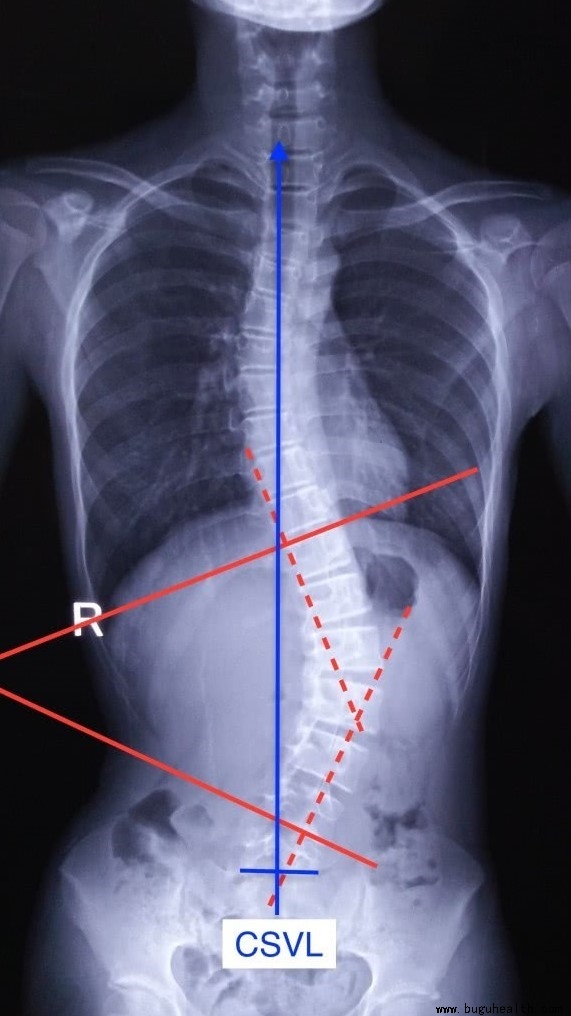

对于脊柱侧弯患者有专门的测量方法:Cobb角。

布骨康复医疗中心

我们也可以用Cobb角的测量方法来测量脊柱矢状面的生理角度。